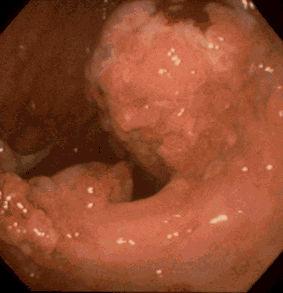

A case of gastric juvenile polyposis with multiple cancers.

Tokyo Pref., Cooperative study between National Cancer Center and Kyushu Cancer Center

Tumor-like lesions/Juvenile polyposis

Stomach/Other

Endoscopy